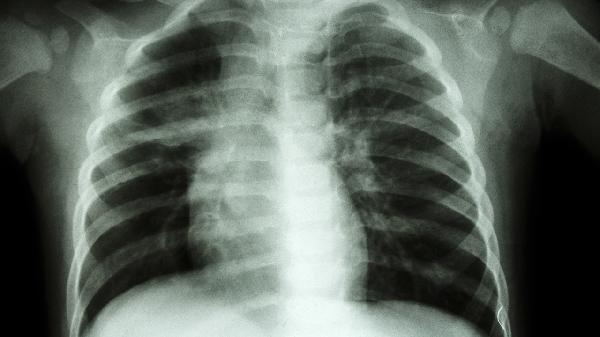

风寒犯肺可以通过一些食疗方法来缓解,比如喝生姜红糖水、吃葱白粥、泡紫苏叶茶、饮用白萝卜蜂蜜饮、以及喝大蒜冰糖水等。这种病症通常是因为受了风寒,常见症状包括咳嗽、鼻塞和流清鼻涕。